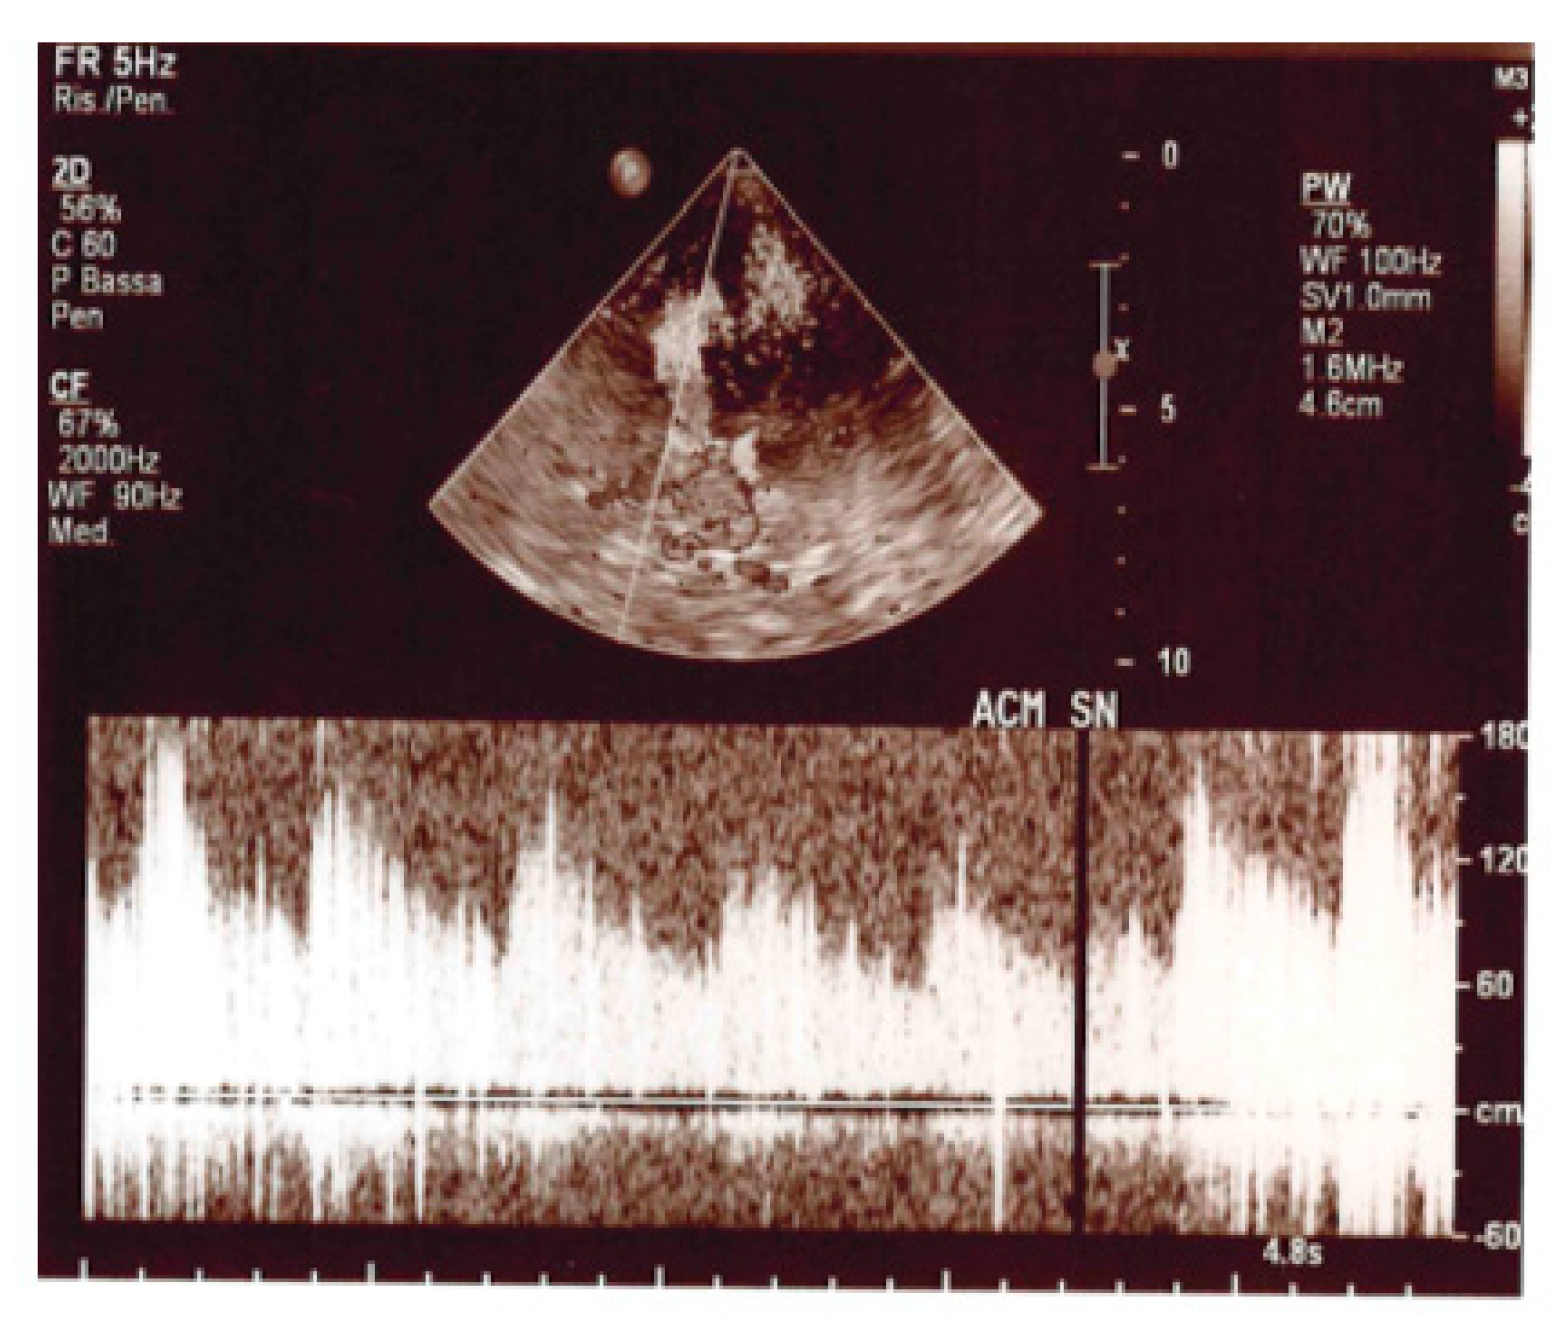

2. Case Presentation